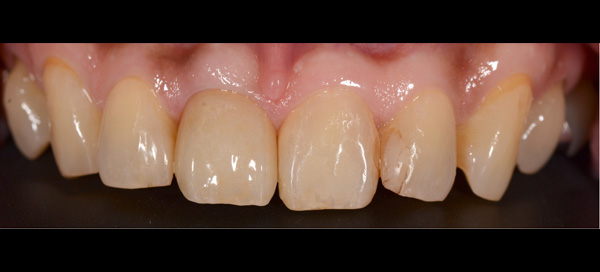

| 主訴 | 前歯が腫れた |

| 治療期間 | 約18ヶ月 |

| 費用 | 700,000円 |

| 治療内容 | インプラント、部分矯正、骨造成、結合組織移植、セラミック修復 |

| 治療に伴うリスク | インプラント周囲炎 セラミックの破折、脱離 |